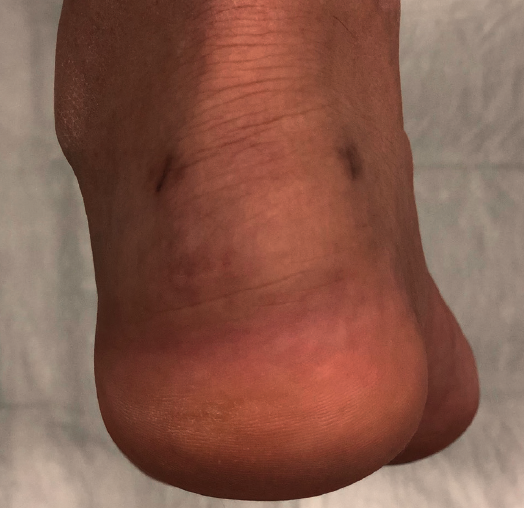

Approximately 6% of the general population will experience some pain episode of the Achilles tendon during life(1). Of these patients, approximately one-third will present tendon insertion damage(2,3). Patients with insertional tendinopathy of the Achilles tendon (ITA) typically experience pain and functional limitation, aggravated by physical activity and following resting periods. They may present thickening of the insertional portion of the tendon, most often at the lateral margin (Figure 1).

Figure 1. Insertional tendinopathy of the Achilles tendon. Thickening of the soft tissues, prominence on the external side.